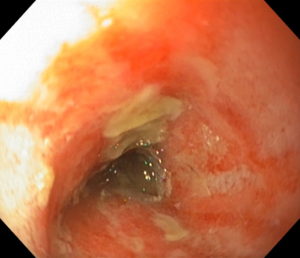

幽門部を確認してみると、ラップのようなものが幽門に栓をするかのように詰まっておりました。

次の写真がその時の内視鏡画像です。

←右のラップのようなものが詰まっており、その先の十二指腸に上のマットようなものも詰まっておりました。

十二指腸はだいぶ荒れてしまっておりました。